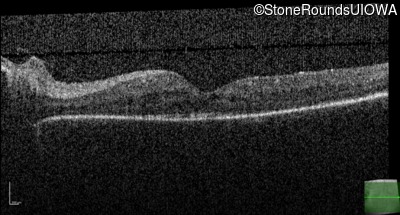

Optical Coherence Tomography - Left - 20/50 -3

Exemplar / OCT Stack